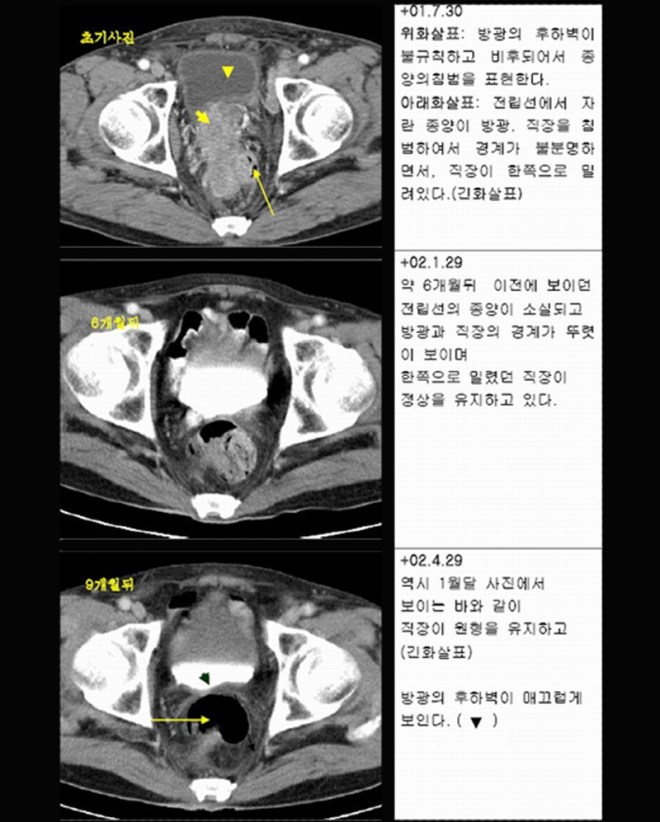

위에서 다루었던 방광암 환자의 이후 record를 수록해 본다. 이 환자는 태음인으로 방광암 4기 진단을 받았고 수신증이 심한 상태였으며, 수술이 불가능하다고 서울대에서 고향으로 내려가서 항암치료를 받아보라고 권유받았던 환자이다. 그리고 위에 1강에서 다루었던 이 한약치료 후에 확연한 감소를 보이기 시작하여서 방사선 치료를 권유하였고, 2017년 6월 28일 다시금 내원하여   진단방사선과 초음파진단을 하였다. 1강에서 실었던 자료를 다시금 실어 본다.

2주간 한약치료를 받고 나서 다소 감소된 결과를 설명하였다.

한달간의 한방치료 약물 G0054를 사용하고 나서, 이후 방사선 치료 4일을 받았을 때의 결과이다.

그리고 한달간의 방사선 치료가 결합된 결과를 어제 보게 되었다.

약 두달간의 치료에 대한  종합적인 결과를 수록해 본다.

이 환자는 두달간의 한약과 한달 동안의 방사선 치료 결과 초기 종양은 대략 83% 정도가 감소되었고, 잔류 종양은 17 % 정도가 남아 있다. 아직 방사선 치료가 끝나지 않았고, 몇 번은 집중적으로 치료를 할 계획이다.